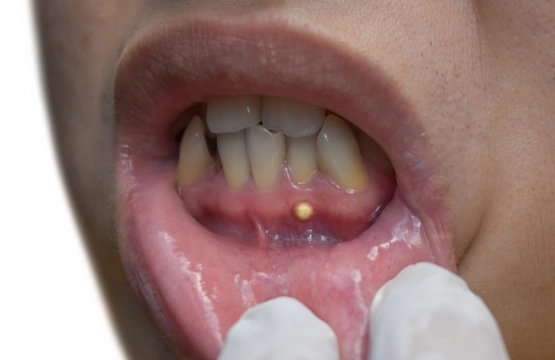

- That "pimple on the gum" (fistula): It might drain a bad-tasting, salty fluid, providing temporary relief.